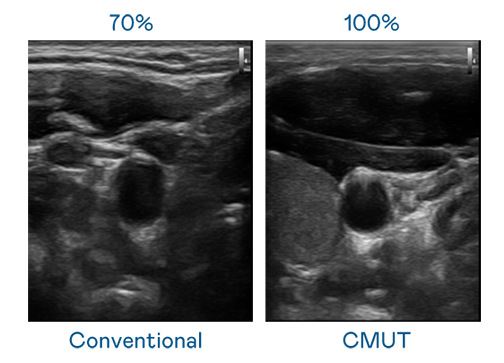

CMUT 技术是一种用电容式微机电元件来产生超音波讯号的技术。与传统 PZT 压电式技术相比,CMUT 频宽增加 30%,更宽频的超音波讯号让影像解析度大幅提升,是实现高影像品质医疗超音波扫描、促进精准医疗发展的关键技术。

超音波影像的解析度高低,首先取决于探头能发出的讯号频宽。恒峰g22 CMUT 可提供高清晰的超音波讯号,提供高频宽、高灵敏度、影像纹理细节更高的超音波影像,协助医护人员缩短影像判读时间及利用精准的医疗影像进行诊断。